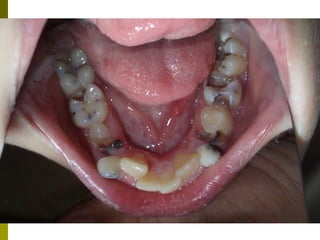

   Οι μασητικές επιφάνειες των οπισθίων δοντιών

ευνοούν την κατακράτηση τροφών και μικροβίων και

συχνά τερηδονίζονται αμέσως μετά την ανατολή τους.

   Έρευνα της Ελληνικής Οδοντιατρικής Ομοσπονδίας

έδειξε ότι σε παιδιά ηλικίας 12 ετών το 83% των

τερηδονισμένων επιφανειών παρατηρείται στις

μασητικές επιφάνειες      (Ουλής Κ.Ι. συν. Ελληνικά

Στοματολογικά Χρονικά 2009’ 53(3)΄97-120)

   Επίσης και μετά από παρακολούθηση έως 10 - 15 έτη, μόνο

το 30 -40% των δοντιών με κάλυψη είχαν μασητικές

αποκαταστάσεις, σε σχέση με 60 -80% των δοντιών χωρίς

καλύψεις.

   Μελέτες έχουν δείξει μείωση της τερηδόνας ,μετά την

τοποθέτηση ΚΟΣ, 85 -37 % μετά από 2 – 6 έτη

    οι προληπτικές καλύψεις θα πρέπει να εφαρμόζονται

ανάλογα με τον βαθμό κινδύνου ανάπτυξης τερηδόνας των

ατόμων, ή των επιφανειών επιλεκτικά και εξατομηκευμένα